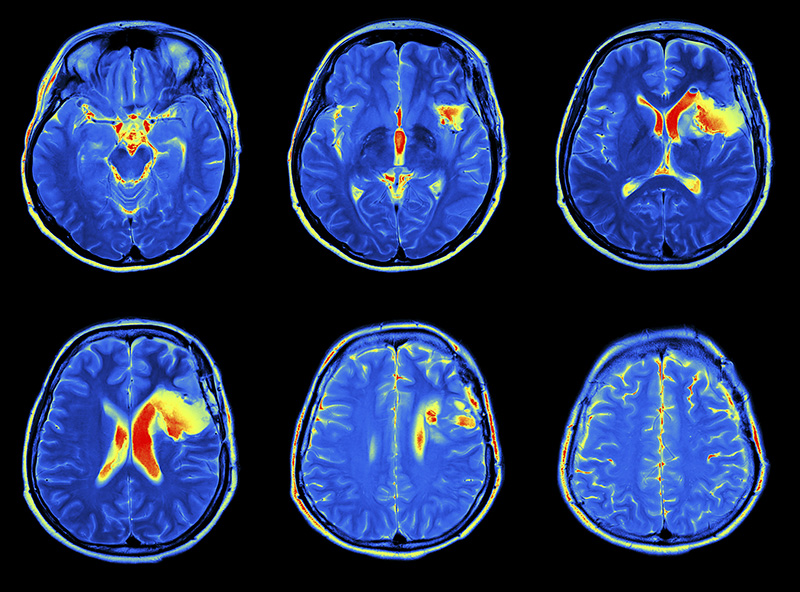

Brain Awareness Night at the NC Science Museum

Brain Awareness Night…

Brain Injury Awareness Day is March 4th, 2020!!

Join NCC as we head to Washington DC to support Brain Injury Awareness Day! See the link below for the order of events! https://www.biausa.org/events/2020-03-04-brain-injury-awareness-day-2020…

March is National Brain Injury Awareness Month

For more than three decades, the Brain Injury Association of America (BIAA) has proudly led the nation in observing Brain Injury Awareness Month by conducting an engaging public awareness campaign…